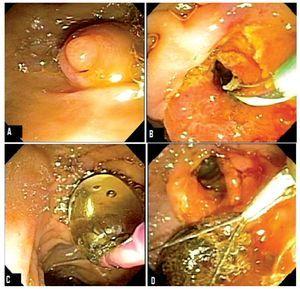

A 69 years old hispanic male with a 4 month history of painless jaundice who was diagnosed elsewhere with unresectable cholangiocarcinoma came to our institution looking for a second opinion and further treatment. Physical exam, except for jaundice was unremarkable. Liver function tests reported total bilirubin 6 mg/dL, direct bilirubin 4 mg/dL, alkaline phosphatase 290 U/L, gammaglutamyl transpeptidase (GGT) 180 U/L, aspartate aminotransferase (AST) 175 U/L and alanine aminotransferase (ALT) 160 U/L. Magnetic resonance cholangiography (MRCP) showed significant intra and extrahepatic bile duct dilatation and a hypointense area within the distal common bile duct (CBD) (Figure 1-A) suggesting a stone. An endoscopic retrograde cholangiopancreatography (ERCP) showed a large stone impacted within the distal CBD (Figure 1-B). The stone could not be retrieved using standard extraction procedures (biliary sphincterotomy, retrieval balloon and/or use of Dormia basket) due to size. Even though mechanical lithotripsy is the modality used most commonly, it was omitted to simplify the process of stone extraction and to reduce costs. In order to choose the right size of the balloon to be used, the bile duct and stone diameters were measured during ERCP with the external diameter (13.2 mm) of the distal end of the duodenoscope (Olympus Evis Exera TJF-160VF). The biliar sphincterotomy was extended and the balloon catheter (CRETM wireguided balloon dilator 15 - 18 mm, Boston Scientific) was passed over a guidewire and positioned at the biliary orifice. Then, the balloon was gradually filled up to 15 mm with water and diluted contrast medium by using an inflation device (ALLIANCE II, Boston Scientific). The fully expanded balloon was maintained in position for 45 seconds after it was collapsed and removed. A Dormia basket was then used to remove the stone. A 25 mm x 30 mm CBD stone was extracted uneventfully except for minor oozing that stopped spontaneously (Figure 2). After the procedure the patient was hospitalized for observation with no clinical evidence of bleeding or pancreatitis; hemoglobin and serum amylase levels were measured 18 hours after the procedure within normal limits. The patient was discharged without complications. One month after the endoscopic intervention no complications were observed.

¿ Figure 2. ERCP images: A) Prominent papilla, B) Large biliary sphincterotomy, C) Large caliber balloon dilation, D) CBD stone extracted with Dormia basket.